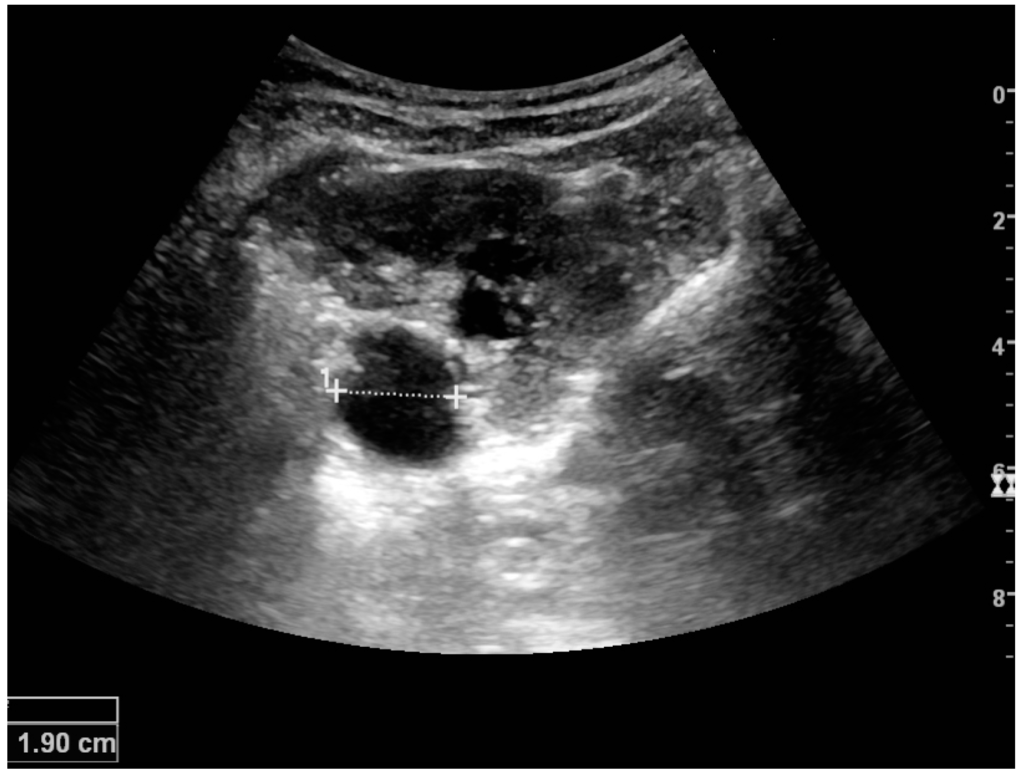

Complex cysts can have membranes dividing the fluid-filled center with internal echoes, calcifications or irregular thickened walls. The complex cyst can be further evaluated with Doppler US, and for Bosniak classification and follow-up of complex cysts, either contrast-enhanced ultrasound (CEUS) or contrast-enhanced computed tomography (CT) are used (Figure 6) [14,15]. The Bosniak classification is divided into four groups going from I, corresponding to a simple cyst, to IV, corresponding to a cyst with solid parts and an 85%–100% risk of malignancy [13,16].

Figure 6. Complex cyst with thickened walls and membranes in the lower pole of an adult kidney. Measurements of kidney length and the complex cyst on the US image are illustrated by ‘+’ and dashed lines.